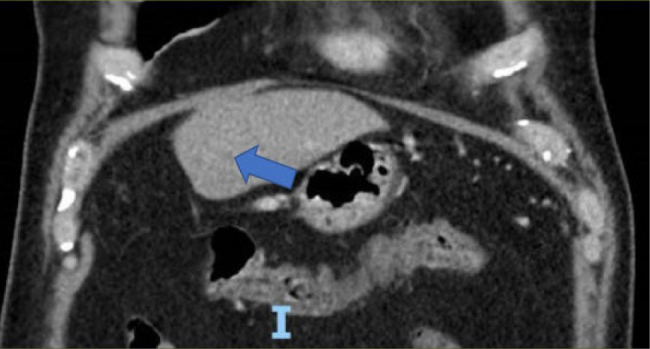

Pancreatic signet ring cell carcinoma (PSRCC) is a rare and aggressive subtype of pancreatic cancer with a dismal prognosis. We present the case of a 50-year-old male who, within six weeks, developed a pancreatic mass with liver metastases. Endoscopic ultrasound-guided biopsy confirmed PSRCC. The presentation of this tumour with distant metastasis after a negative computed tomography (CT) of the abdomen and pelvis six weeks prior underscores the highly aggressive nature of PSRCC and the crucial need for heightened clinical suspicion, especially in cases with persistent or atypical abdominal pain. This case highlights the limitations of current diagnostic modalities and emphasises the urgent need for further research into improved early detection methods, molecular characterisation and effective treatment strategies for this rare and lethal subtype of pancreatic cancer.

Learning points: Aggressive malignancy can become metastatic within six weeks of a negative CT scan.A CT scan may not detect a small pancreatic lesion <2 cm.